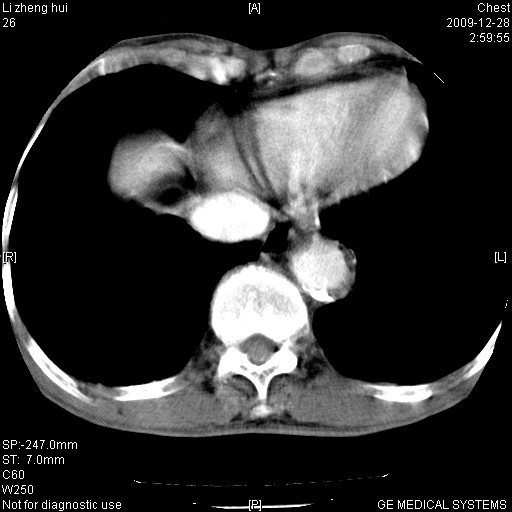

标题: CT23859:胸主动脉瘤

男  79岁 胸部痛急诊入院,晚上做的增强

考虑主动脉瘤?(增粗、钙化、壁血栓?)

动脉瘤伴附壁血栓

1)考虑胸主动脉壁间血肿或夹层动脉瘤。2)多发性肝囊肿。

1)考虑胸主动脉附壁血栓或夹层动脉瘤。2)多发性肝囊肿。